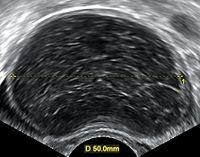

- Transvaginal ultrasonography showing a 67 x 40 mm endometrioma, with a somewhat grainy content.

Ovarian cysts are usually diagnosed by ultrasound, CT scan, or MRI, and correlated with clinical presentation and endocrinologic tests as appropriate.[10]

Ultrasound

Follow-up imaging in women of reproductive age for incidentally discovered simple cysts on ultrasound is not needed until 5 cm, as these are usually normal ovarian follicles. Simple cysts 5 to 7 cm in premenopausal females should be followed yearly. Simple cysts larger than 7 cm require further imaging with MRI or surgical assessment. Because they are large, they cannot be reliably assessed by ultrasound alone; it can be difficult to see posterior wall soft tissue nodularity or thickened septation due to limited ultrasound beam penetrance at this size and depth. For the corpus luteum, a dominant ovulating follicle that typically appears as a cyst with circumferentially thickened walls and crenulated inner margins, follow up is not needed if the cyst is less than 3 cm in diameter. In postmenopausal patients, any simple cyst greater than 1 cm but less than 7 cm needs yearly follow-up, while those greater than 7 cm need MRI or surgical evaluation, similar to reproductive age females.[11]